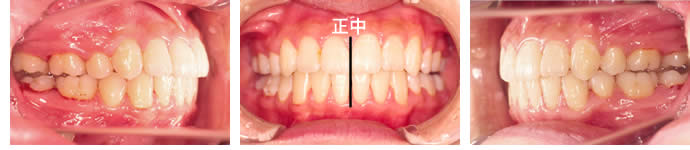

■治療前

正中(歯並びの真ん中)が、ほぼ1歯分ずれています。叢生も強く、犬歯が八重歯状になっています。